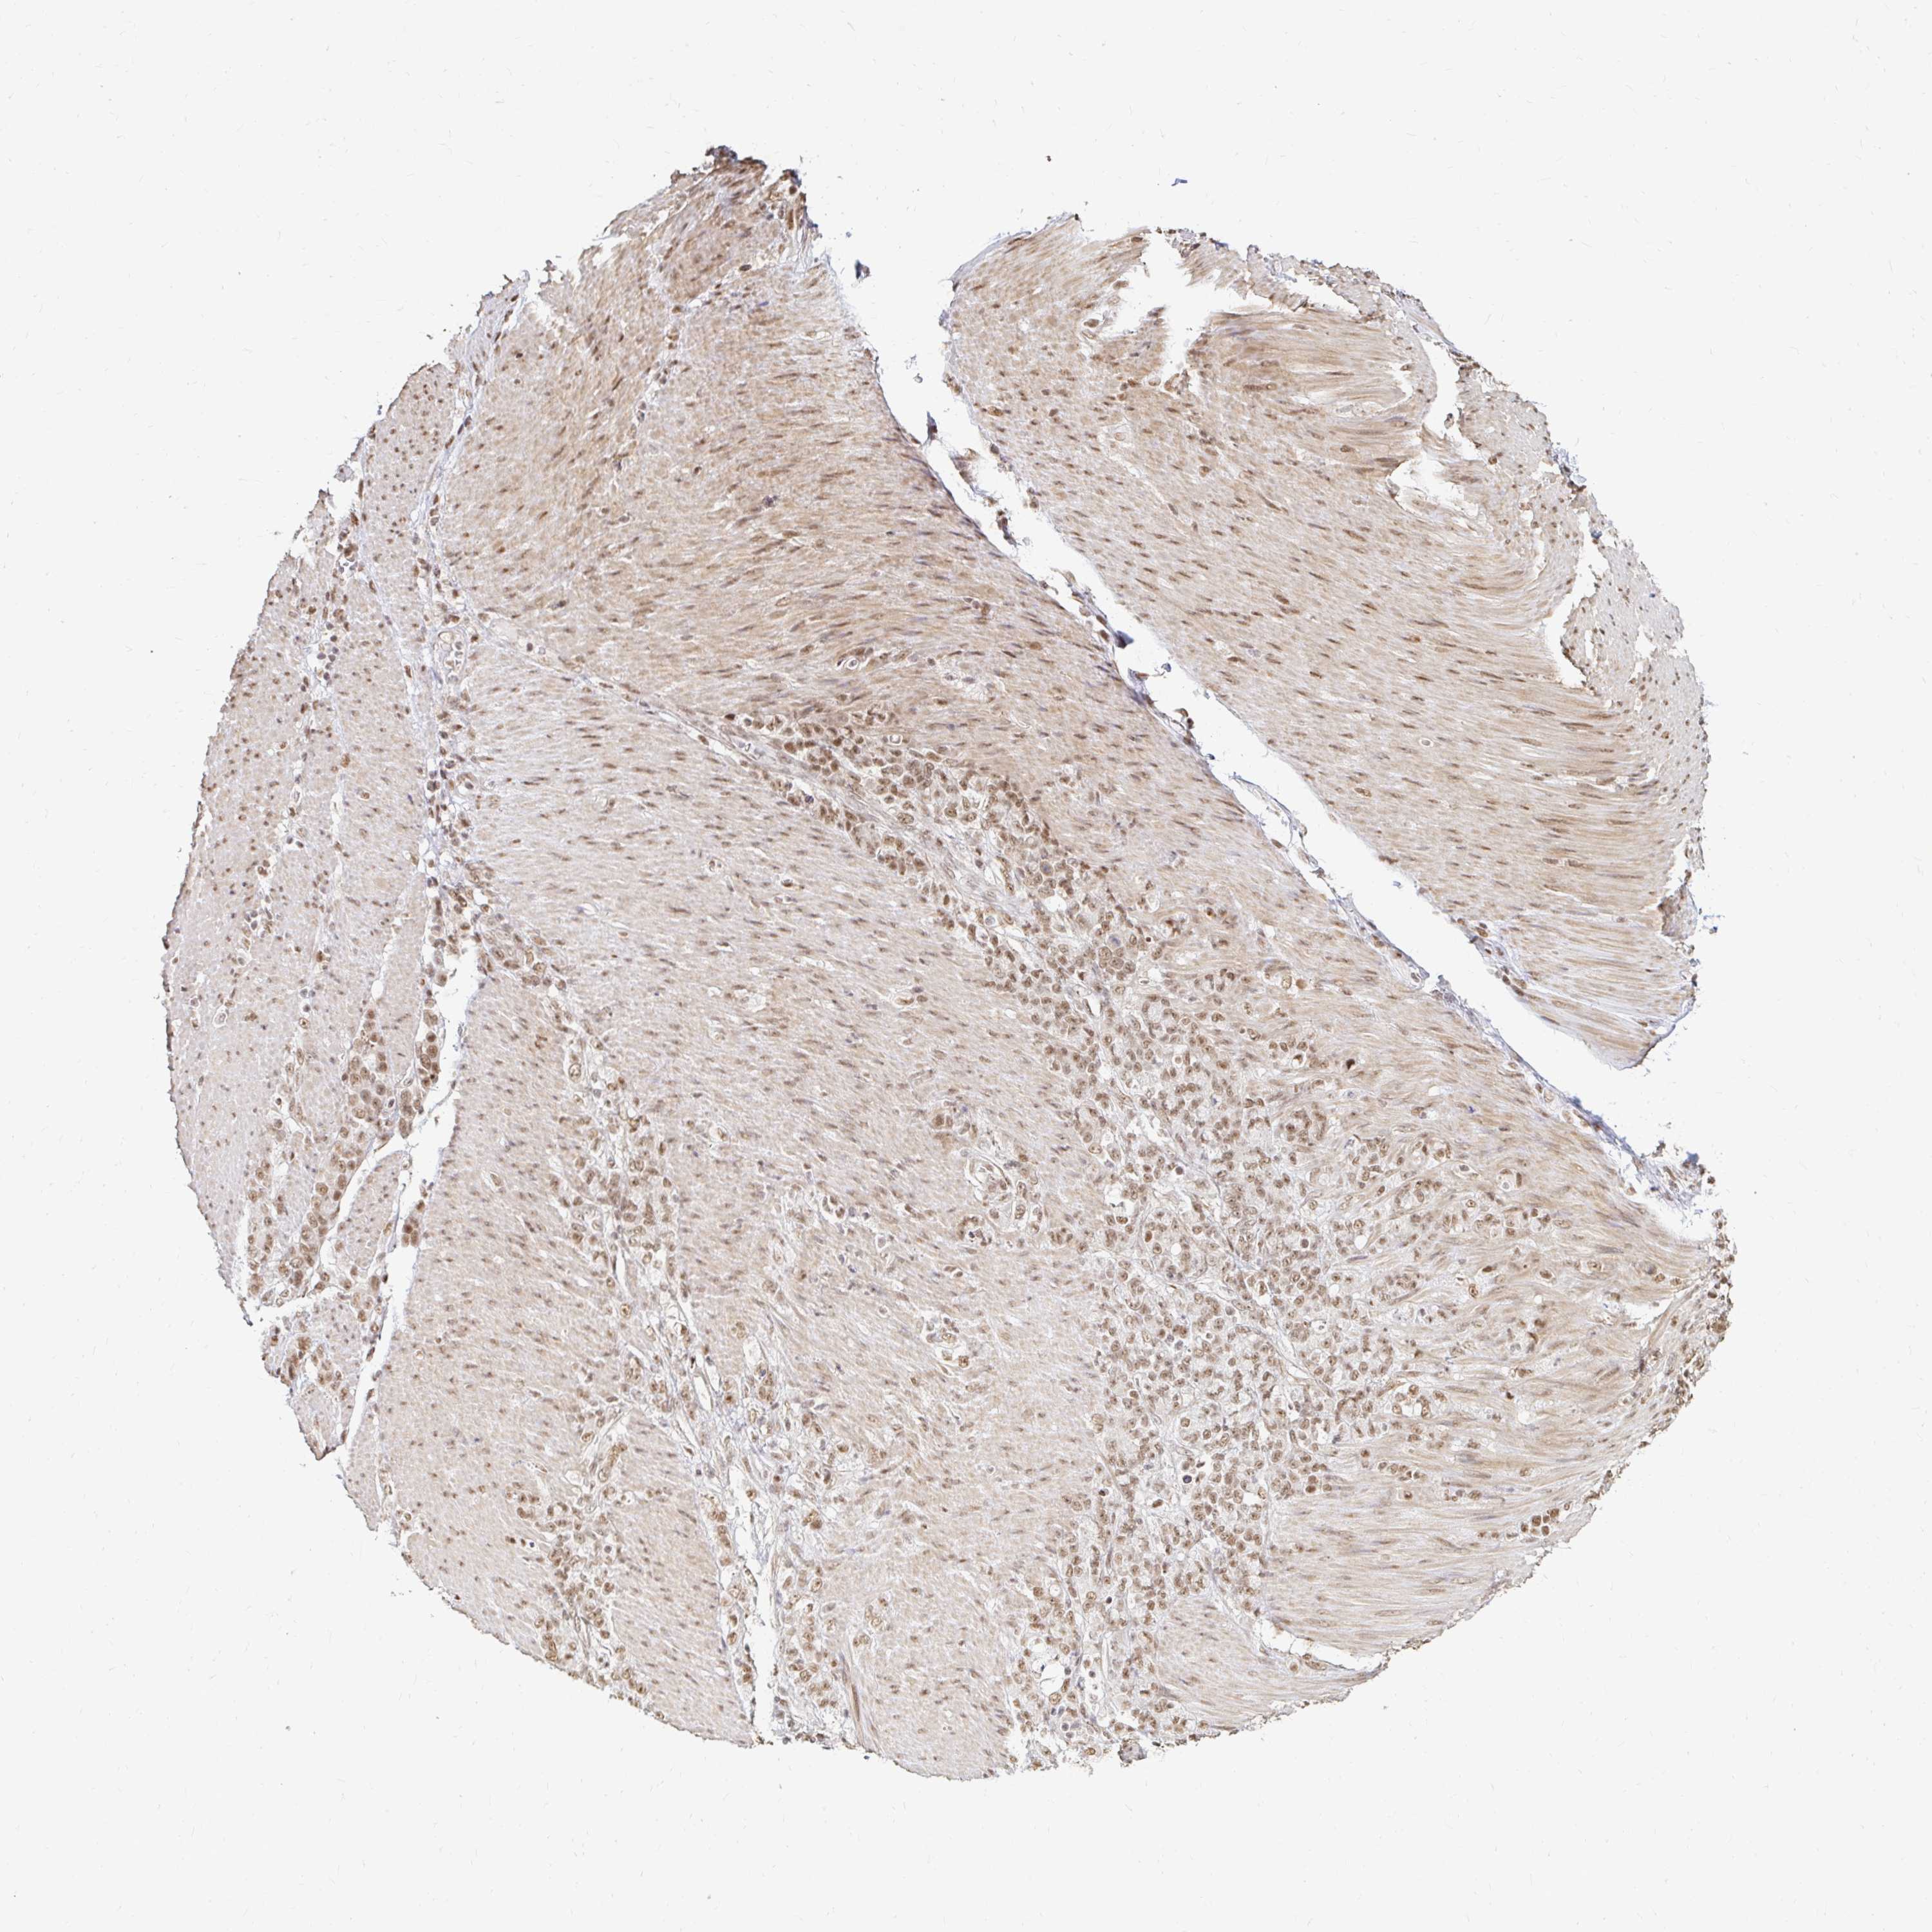

STOMACH CANCER - Protein expressioni

A mouse-over function shows sample information and annotation data. Click on an image to view it in a full screen mode. Samples can be filtered based on level of antibody staining by selecting one or several of the following categories: high, medium, low and not detected. The assay and annotation is described here.

Note that samples used for immunohistochemistry by the Human Protein Atlas do not correspond to samples in the TCGA dataset.

Antibody stainingi

Antibody staining in the annotated cell types in the current human tissue is reported as not detected, low, medium, or high, based on conventional immunohistochemistry profiling in selected tissues. This score is based on the combination of the staining intensity and fraction of stained cells.

Each image is clickable and will lead to virtual microscopy that enables deeper exploration of all samples and also displays staining intensity scores, fraction scores and subcellular localization as well as patient and tissue information for each sample.

Antibody HPA041057

Antibody HPA058707

Antibody CAB011532

Staining

High

Medium

Low

Not detected

Intensity

Strong

Moderate

Weak

Negative

Quantity

>75%

75%-25%

<25%

None

Location

Nuclear

Cytoplasmic/membranous

Cytoplasmic/membranous,nuclear

Adenocarcinoma, NOS

Adenocarcinoma, High grade